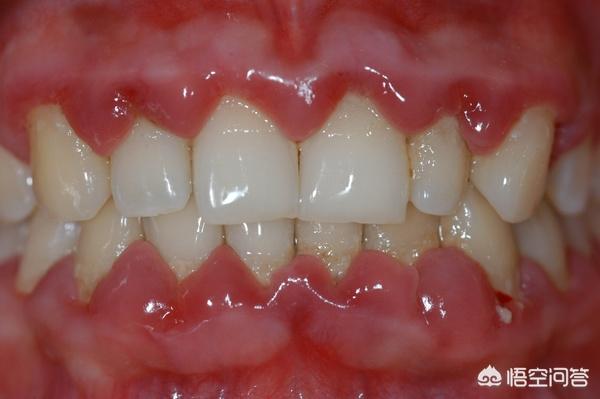

临床以微生物感染造成牙周炎症性出血,进而引起结缔组织和骨破坏为主要表现。牙周病造成的组织损害是不可逆的,如果不经过专业、系统的治疗非但不能自愈反而会愈发严重导致最后牙齿丧失支持松动脱落。

2、牙龈红肿程度比较严重,如果是牙龈炎,牙龈最多红红的,有时候刷牙可能会出血,但是牙周炎的话,肿胀可以看得出来,尤其是牙龈乳头经常有不适感,简单来说牙龈萎缩,牙根暴露强烈酸痛。

通过牙周手术切断致病源,并且定期去医院检查牙周,长期治疗直至牙周恢复健康。